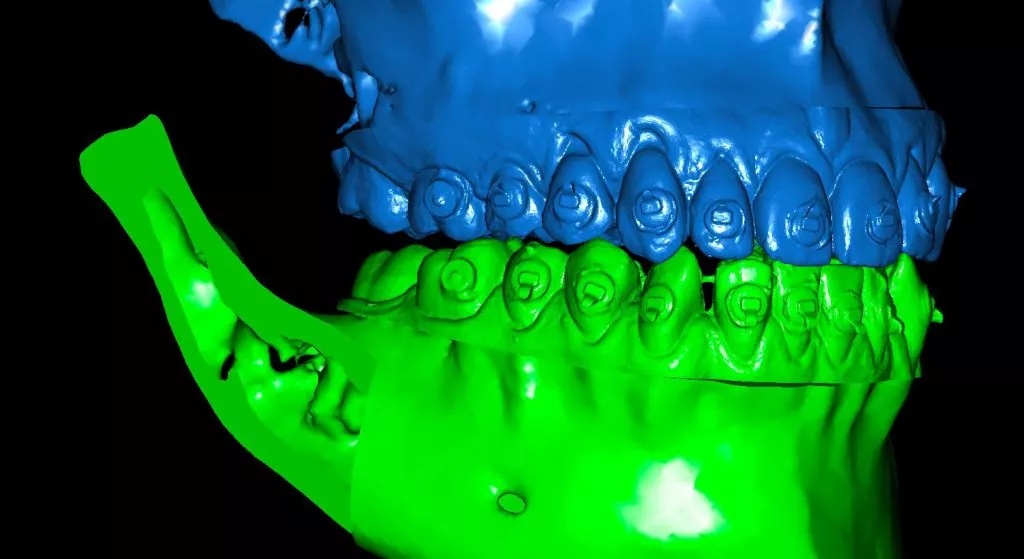

ישנם כיום כלים טכנולוגיים תלת מימד להדמיה של התהליך הכירורגי ולתכנון מדויק של תוצאותיו.